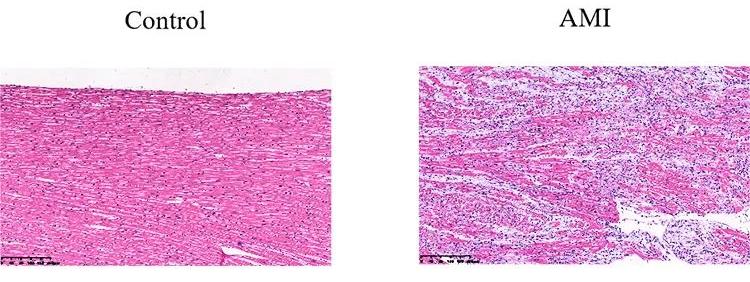

檢測指標(biāo):病理學(xué)HE染色和免疫組化分析心肌損傷。

病理HE染色示意圖